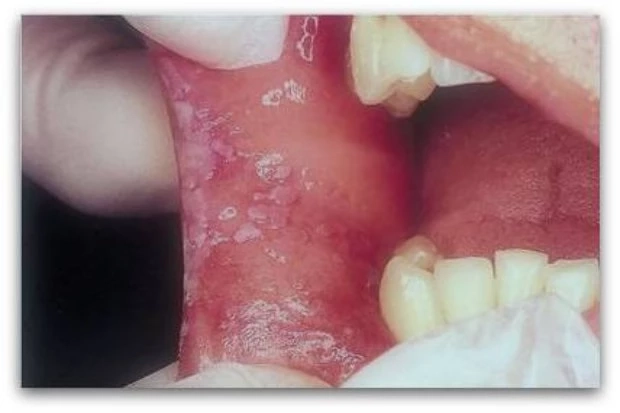

เช่น การสูบบุหรี่ ดื่มเหล้า การเคี้ยวหมาก การติดเชื้อไวรัส Human papilloma virus (HPV) หรือการมีแผลเรื้อรังในช่องปาก เป็นต้น อาการส่วนใหญ่ของมะเร็งในช่องปากพบได้หลายลักษณะ เช่น การมีฝ้าขาวๆ ที่บริเวณใต้ลิ้น เหงือก พื้นช่องปาก เมื่อมีอาการเรื้อรังเป็นเวลานานรอยฝ้านั้นอาจนูนขึ้นเป็นก้อน

หรือกรณีเกิดแผลจะมีลักษณะคล้ายอาการร้อนในแต่จะมีอาการเรื้อรังมากกว่า 1 เดือน มีเลือดไหลในช่องปากโดยไม่ทราบสาเหตุ มะเร็งของลิ้นหรือลำคอในบางตำแหน่งอาจทำให้เกิดการเจ็บในหูขณะกลืนอาหารได้เนื่องจากมีเส้นประสาทร่วมกัน หากมีอาการผิดปกติดังกล่าวผู้ป่วยควรรีบปรึกษาแพทย์เพื่อการวินิจฉัยและรักษาตั้งแต่ในระยะไม่ลุกลาม